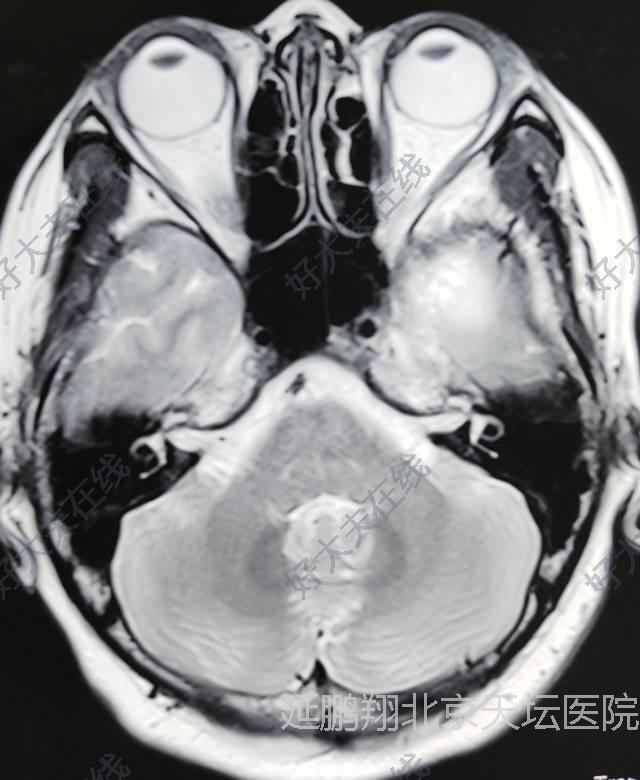

患者女性,38岁。间断性头痛3年左眼视力模糊1年。核磁显示左侧前床突脑膜瘤。

患者恢复顺利。复查核磁肿瘤消失。